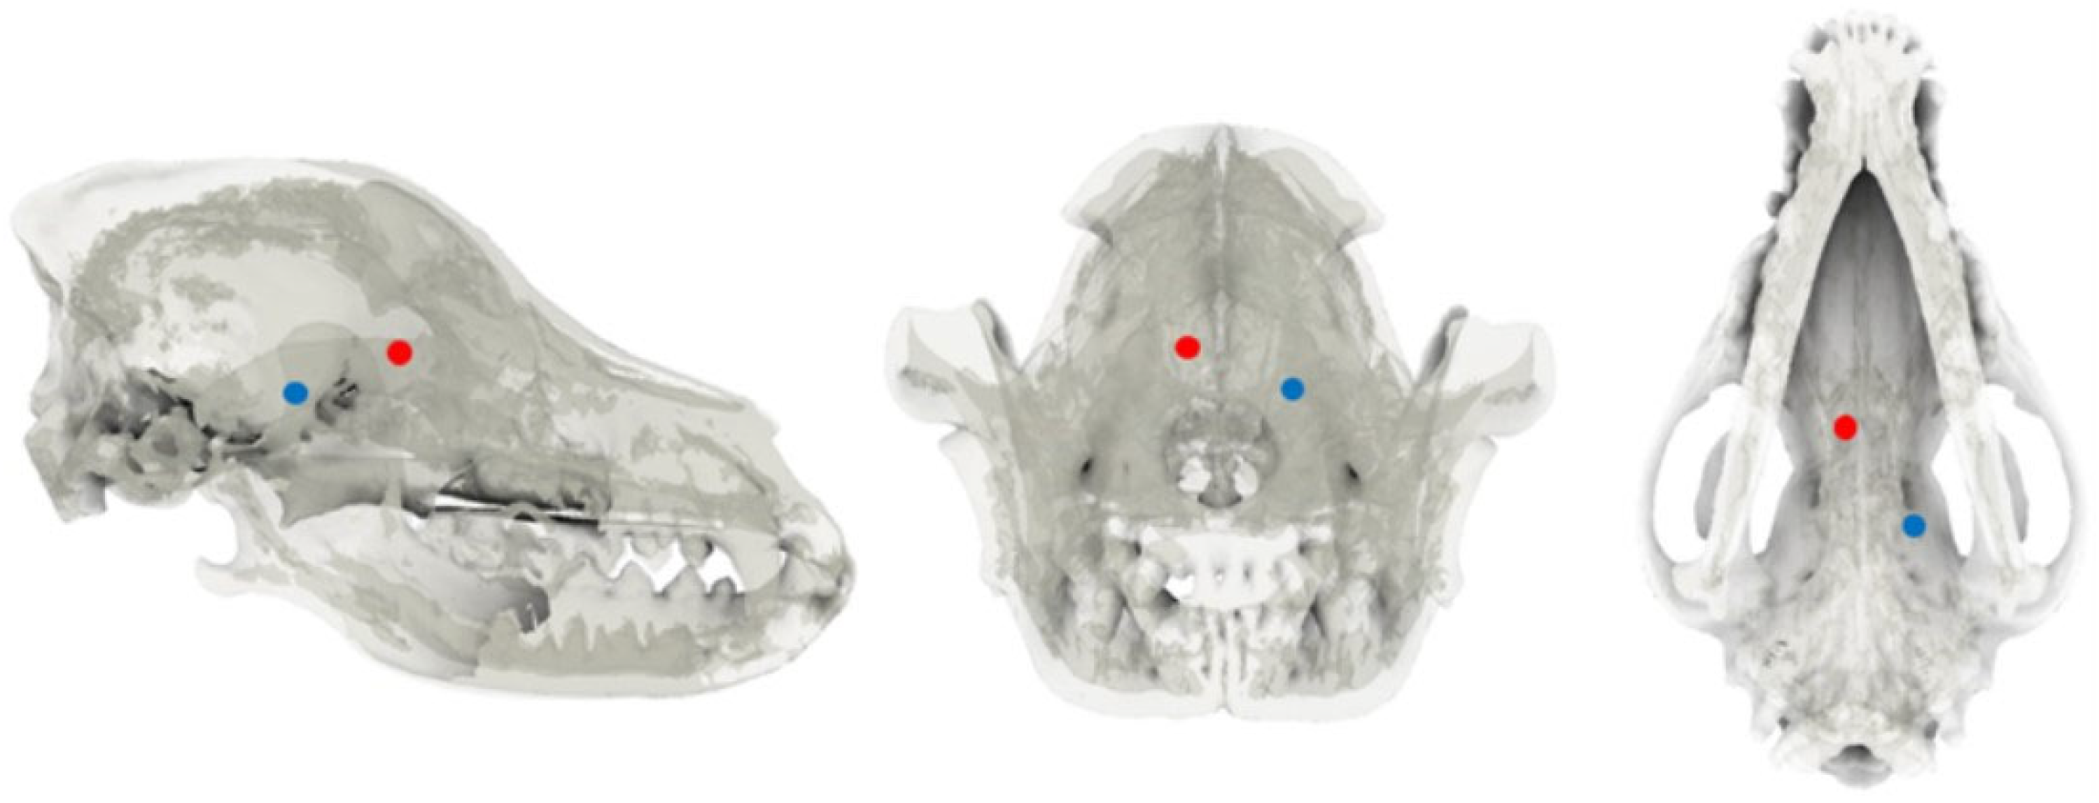

The skull was adjusted to 10% transparency and realigned along the X, Y, and Z axes. In the dorsal plane, the internasal suture to the external sagittal crest was aligned along the X-axis, while in the transverse plane, the zygomatic processes of the frontal bone on both sides were horizontally positioned. The frontal sinus, frontal lobe, and olfactory lobe were identified in the sagittal plane, and the symmetrical regions were adjusted to overlap as closely as possible along the X-Z plane. To establish the target area and for the injection of the tumor model, spherical markers with a diameter of 1.5 mm were placed in the right fronto-olfactory and left piriform lobes to visualize the ROIs (Figure 1).

Figure 1. Tumor location selection. After reducing skull opacity, the sagittal, transverse, and dorsal planes were examined. The fronto-olfactory lobe region of interest (ROI) was identified and marked with a red sphere, while the piriform lobe ROI was delineated with a blue sphere.